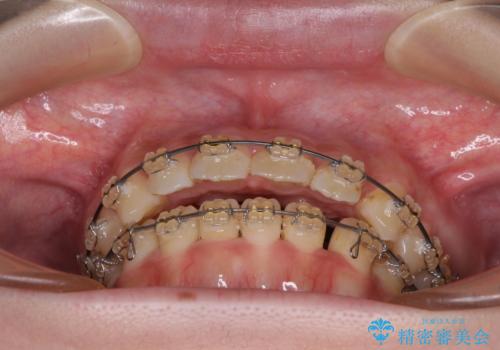

- 大学病院にて装置を装着したものの、治療が十分に受けることができないとのことで転院をされた患者様です。

上顎歯列が前方にあり、口元が閉じにくくなっていたため、既に装着されている装置を使用して上顎歯列全体を後方に移動させていくこととしました。

舌の突出癖があり、それが原因で上下前歯に隙間ができていたため、改善のためのトレーニングを行うように指示をしました。

舌の突出癖の影響か、なかなかスペースが閉じきらず、治療期間は予定よりも長期間となりました。

舌突出癖改善のトレーニングの重要性を認識することとなりました。